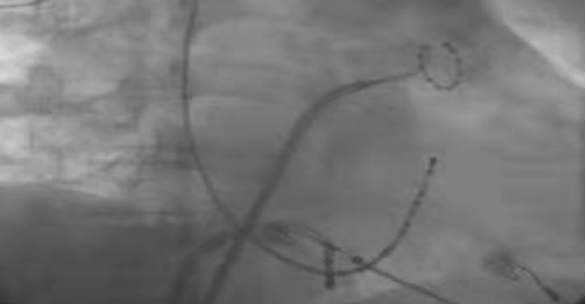

image.png

图二:术中DSA影像图